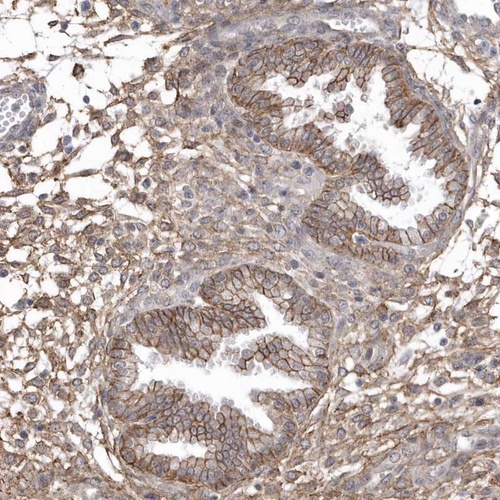

Immunohistochemical staining of human corpus, uterine shows moderate membranous and cytoplasmic positivity in glandular cells.